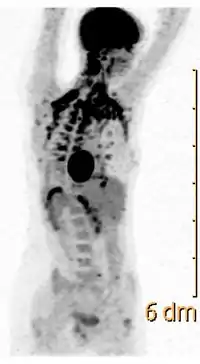

У людини диференціація фібробластів «преадипоцитів» у буру жирову тканину розпочинається на 20-му тижні розвитку. У час народження вона становить приблизно 1 % від загальної маси тіла[3] (близько 30 г[4]). Бурий жир розташований навколо кровоносних судин, що постачають кров'ю головний мозок та органи черевної порожнини, а також оточує підшлункову та надниркові залози і нирки[3]. Найбільші його скупчення спостерігаються між лопатками, у антеріолатеральній ділянці шиї та передній стінці черевної порожнини[2]. Завдяки бурому жиру життєво важливі органи немовляти не охолоджуються у середовищі з низькою температурою[3].

Після народження у немовлят починає розвиватись біла жирова тканина, а бура зникає. У дорослому стані в людей зовсім немає окремих місць скупчення бурого жиру, проте серед всіх адипоцитів зберігається приблизно 1 % бурих, що хаотично розкидані серед білих. Також в дорослому організмі залишаються преадипоцити, що за відповідної стимуляції можуть перетворюватись у бурий жир, зокрема під час адаптації до хронічного переохолодження. Також преадипоцити можуть диференціюватись у буру жирову тканину, розміщену приблизно так, як у новонароджених, під впливом високих концентрацій адреналіну та норадреналіну, які спостерігаються у хворих на феохромоцитому (пухлину надниркових залоз)[3].